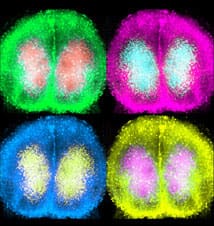

Led by postdoctoral researcher, Marco Brancaccio, the group exploited a new genetically specific way of controlling biochemical signalling pathways in nerve cells, a method known as “pharmacogenetics”. The group monitored the cell- and circuit-level timing by imaging circadian rhythms of clock gene activity in cultures of SCN tissue from genetically modified mice. They controlled in a very specific way individual biochemical signalling pathways in targeted SCN neurons, and revealed a central role for the Gq/calcium signalling pathway in allowing the SCN to encode 24-hour time within its neural circuit. This provided a completely new perspective on how the circadian clock of the brain keeps accurate 24-hour time.